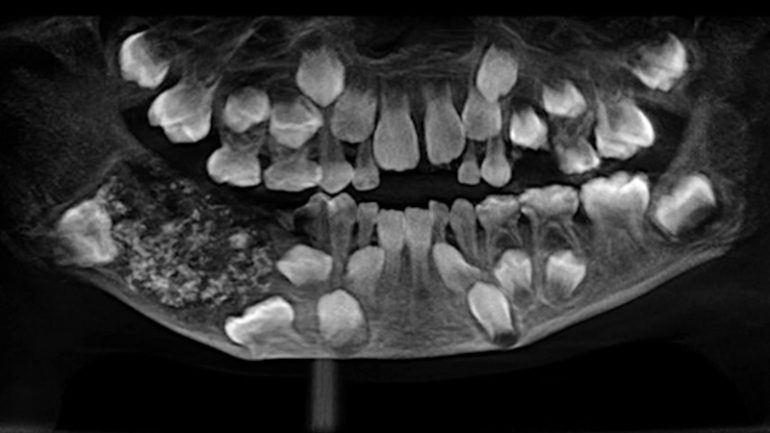

X光顯示男童的顯示下巴組織重達200公克,包含了526顆牙齒。

據印度時報報導,這些牙齒中有些只有0.1毫米,有些則高達15毫米,但都具有牙齒、牙冠和臼齒。該手術做了5小時,執刀醫生 Herald 說:「就像是牡蠣裡面跑出珍珠一樣。」